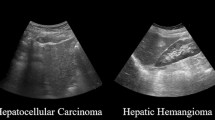

Compared to the image diagnosis using dataset of other photo images, US images are more heterogeneous for the CAD in terms of their image parameters, setting of equipment, and condition of examination [14,15,16,17,18]. To date, several studies have shown the effectiveness of machine learning for the diagnosis of focal liver lesions by a B-mode ultrasound image (Table 1). For example, Hwang et al. [19] tried to extract textural features of focal lesions such as cysts, hemangiomas, and malignant lesions for the diagnosis of a liver tumor; they demonstrated high diagnostic accuracy among all focal liver lesion groups. Contrast-enhanced US (CEUS) was also applied for more accurate diagnosis of liver tumors [20, 21]. Kondo et al. [22] reported the automatic classification of benign tumors, hepatocellular carcinoma, and metastatic tumors using machine learning of the CEUS image. They used a contrast agent, Sonazoid, and found that sensitivity, specificity, and accuracy that distinguish malignant lesions from benign were 94.0%, 87.1%, and 91.8%, respectively. Another report applied a multiple kernel learning-based framework, achieving accuracy of more than 90% for the different diagnosis of benign and malignant liver tumors using CEUS images [23]. Although, some studies applied neural network for CAD of focal liver lesions, their accuracies are similar to those by support vector machine, probably because of the limited size of training cohort. However, it is expected that development of deep neural network-based CAD using larger dataset should help to achieve more accurate and refined US diagnosis of focal liver diseases, such as that reported in CAD for retinopathy and skin lesions [10, 12].

Firstly, for the development of computer-aided or artificial intelligence (AI)-aided US diagnosis, deep learning for disease screening, which can detect the pathological findings and distinguish them from the physiological image, should be required. Secondly, a function for the differential diagnosis of the lesion is also needed (Fig. 1). Because there is a complex normal architecture consisting of vessels and the bile duct in the liver with anatomical anomalies, the pattern of still images in each segment of the liver that are restricted by the position and direction of the probe should be unified among operators to distinguish pathological abnormalities from normal structures [34]. In addition, for the development of deep leaning algorithm for different diagnoses of hepatic lesions, supervised image data, where specific lesions and definitive diagnoses are linked, should be essential. After the learning of still image data and the diagnosis process of the disease, a database of movie images taken in the unified order throughout the entire part of the liver needs to be constructed. Video images of Doppler US and CEUS are also optical materials in the development of a robust AI algorithm for diagnosis.

Workflow for the development of deep learning-based diagnosis system in ultrasonography. The application of deep learning technology for ultrasonography (US) image diagnosis consists of two steps. Firstly, deep learning using supervised images data of pathological lesions is required. At this point, recognition of the lesions is performed by the operators. This step aims at achieving accurate diagnosis through deep learning; both focal (such as liver cancer and benign tumors) and diffuse liver lesions (such as fatty liver and liver cirrhosis) are required using still image (including B-mode and elastography-based images), and movie image (B-mode, contract-enhanced US, and color Doppler images). Secondly, for the development of deep learning-based screening system, a database that includes normal liver images and artifact images needs to be constructed. In this step, computer (or artificial intelligence: AI) is required to detect pathological lesions. The segments and detailed portion, where the lesions exist, also need to be determined. For this purpose, position of normal structure consists of many vessels and ducts should be recognized by AI; still and movie images database should be analyzed. Fusing these technologies will facilitate the next-generation AI-equipped US